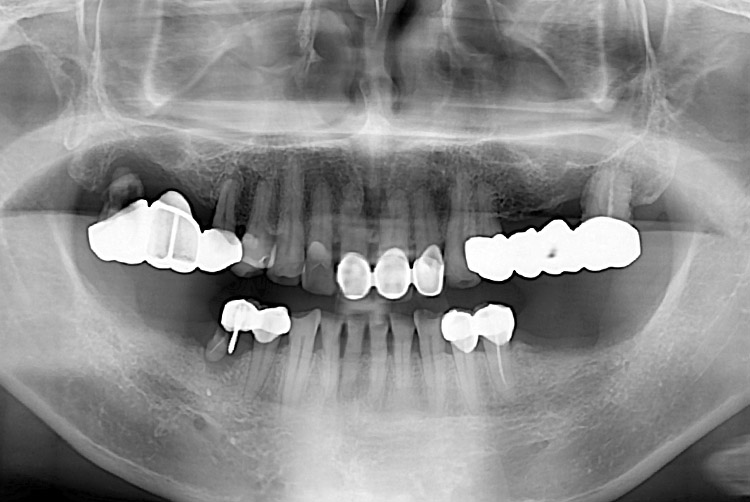

[임플란트] 임플란트

치료전 : 2017-12-18